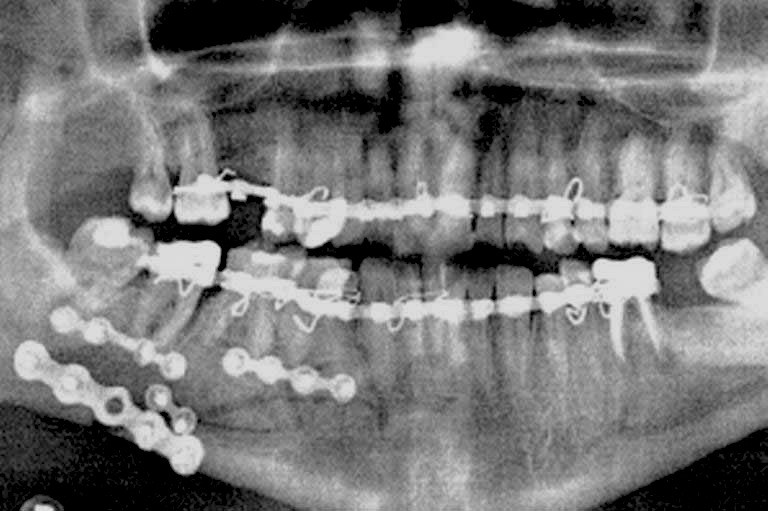

این جراحی به منظور مرتب کردن دندانهایی که با انجام ارتودنسی قابل درمان نیستند انجام میشود. در واقع مشکلات فک و دندان میتوانند مادرزادی، ژنتیکی و تکاملی باشند پس ممکن است در بدو تولد و یا در رشد فرد نیز به وجود آیند و باعث بدشکلی دندان و فک فرد شوند برای درمان این ناهنجاری باید جراحی فک صورت گیرد.

این جراحی توسط متخصص و جراح فک و صورت برای اصلاح ناهنجاریهای دندانی و اسکلتی مانند نامرتب بودن دندانها و فک انجام میشود. اگر فردی در ناحیه فک پایین دچار شکستگی شود با انجام جراحی فک پایین عملکردهایی چون صحبت کردن، تنفس، جویدن غذا و ... بهبود مییابد. با انجام این جراحی ممکن است که در ظاهر فرد تغییر چشمگیری ایجاد شود ولی این جراحی بیشتر برای بهبود عملکرد فک انجام میشود.